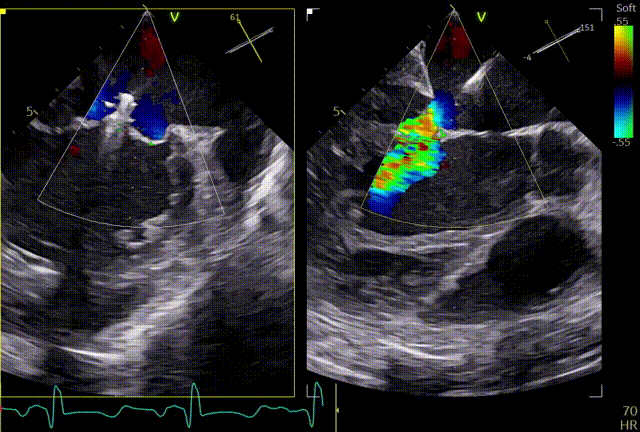

术前TTE

两腔心

短轴

四腔心zoom模式

反流情况